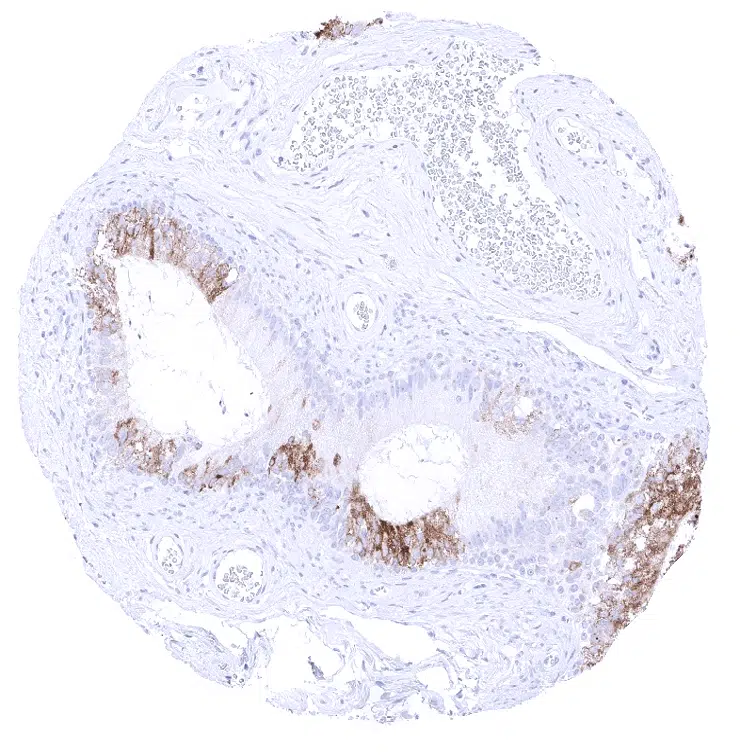

Liver – A strong MUC6 staining is regularly seen in small juxtaportal bile ducts while large bile ducts are MUC6 negative.